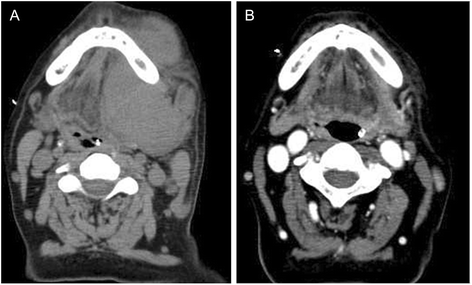

实验目的是明确患者的肿瘤类型、分期及病理特征,为后续治疗方案选择提供依据。方法细节为:对58岁无HIV感染史的男性患者进行临床检查、计算机断层扫描(CT)、口腔肿瘤组织活检(苏木精-伊红染色、免疫组化(IHC)、EB病毒编码RNA原位杂交、染色体核型分析)及骨髓穿刺检查。结果解读:CT显示口腔内巨大肿瘤(无淋巴结肿大,如图1a所示),苏木精-伊红染色可见中心母细胞形态的大淋巴细胞,免疫组化结果显示肿瘤细胞CD138、CD38、CD56、MUM-1阳性,CD20、CD79a、BCL-6阴性,EB病毒及HHV8检测阴性,Ki-67增殖指数接近100%(n=1,P未明确),染色体核型异常,骨髓穿刺显示肿瘤细胞浸润,最终诊断为IVA期口腔PBL。

实验目的是评估硼替佐米对化疗耐药的口腔PBL的治疗效果。方法细节为:入院第9天开始给予硼替佐米治疗,剂量为1.3mg/m²,分别在第1、8、15天给药,第一周期未联合地塞米松,第二周期联合地塞米松治疗;治疗过程中监测肿瘤大小、血清乳酸脱氢酶(LDH)水平等指标。结果解读:硼替佐米治疗1周后,口腔肿瘤显著缩小,1个月后口腔无明显肿胀(CT检查证实,如图1b所示),血清LDH水平快速下降;但第三周期后出现硼替佐米耐药,改用EPOCH方案联合放疗,患者最终在诊断后5个月因疾病进展死亡(n=1,P未明确)。产品关联:文献未提及具体实验产品,领域常规使用硼替佐米注射剂等抗肿瘤药物。